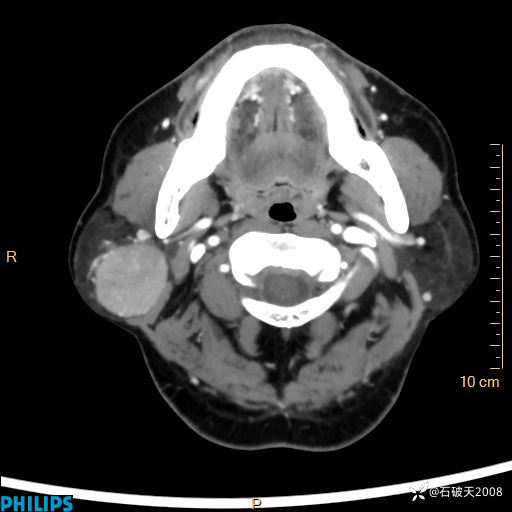

病例分享:颈部占位,一周后公布病理

男 57岁 主 诉:发现右侧颌下肿物1月余。

现病史:1月余前家属发现右侧颌下肿物。局部皮肤无红肿、热痛,无吞咽困难,无异物感,无恶心、呕吐,无头痛、头晕,无胸闷、胸痛,无发热、咳嗽、咳痰及呼吸困难。于我院行体表肿块彩超检查(2024.03.15我院)示:右侧耳下皮下软组织内低回声,未治疗。今为进一步治疗门诊以“腮腺肿瘤”为诊断收住我科,发病来患者神志清,精神可,饮食、睡眠及大小便正常,体重无明显下降。

静脉期